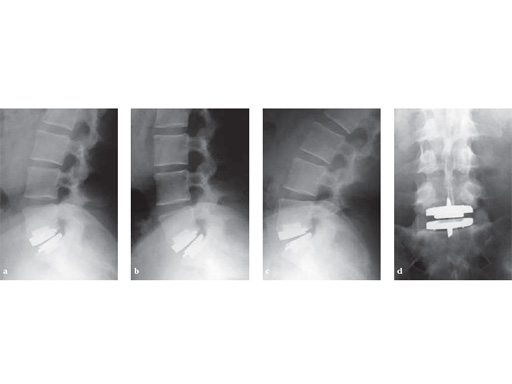

Case 1

44-years-old Firefighter2 years of increased low back pain